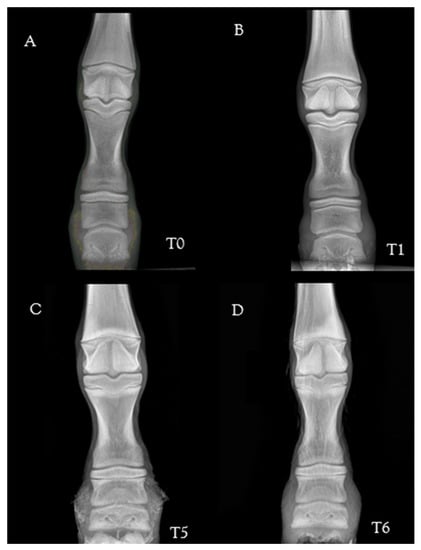

2.3. Radiological Parameters